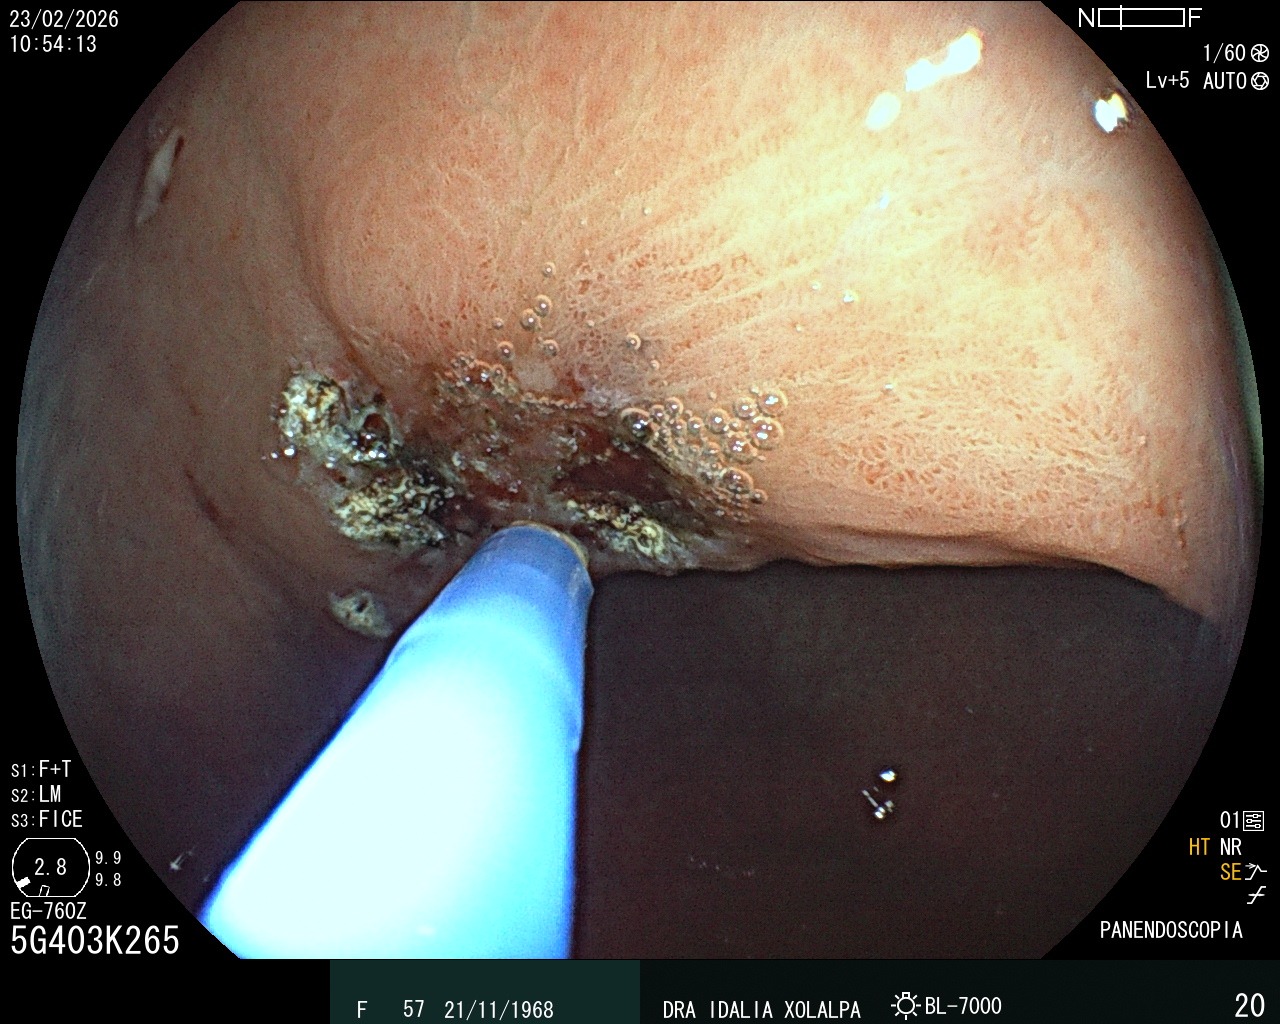

Terapia con Argón

Terapia con plasma de argón endoscópica